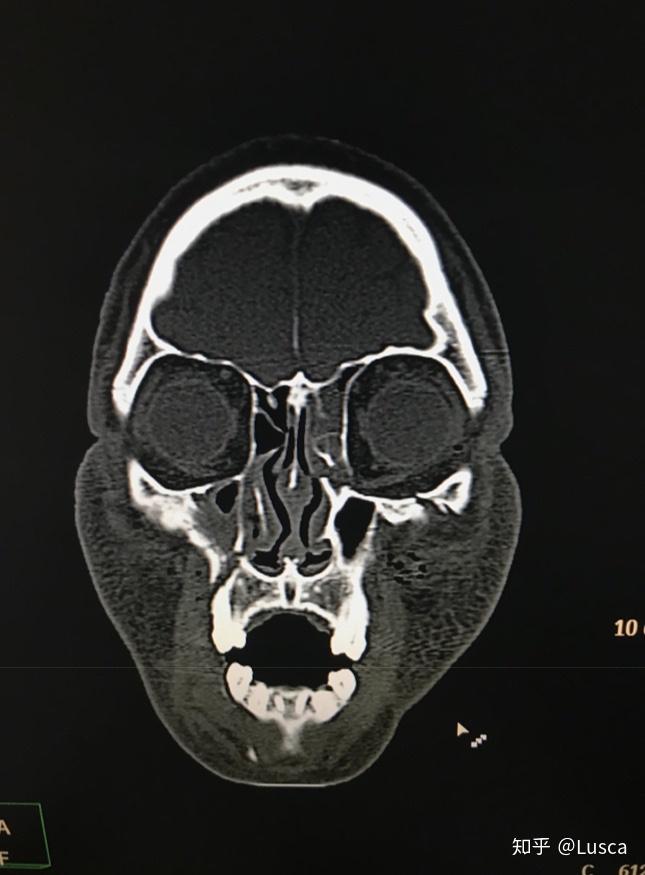

诊断 处理 上颌骨lefort-i骨折,下颌骨颏部骨折.